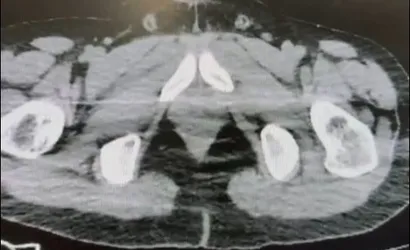

Ekiplerin sokak satıcılarına yönelik çalışmalarını yoğunlaştırması sonucu, şüpheliler S.B. ve O.R.'nin "yutma yöntemi" ile kente uyuşturucu madde sevk edeceği bilgisi üzerine operasyon düzenlendi. Şüphelilerin ikametlerinde ve araçlarında aramalar yapıldı.

Aramalarda; 101 kapsül halinde 722 gram uyuşturucu madde, 1 adet hassas terazi, yutma yönteminde kullanılan muhtelif materyaller ile uyuşturucu ticaretinden elde edildiği belirtilen 20 bin 210 TL, bin 320 euro ve 10 ABD doları ele geçirildi.